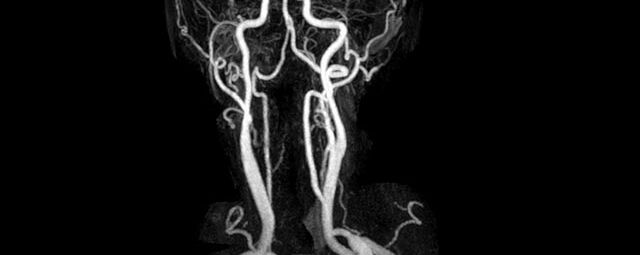

Halsgefäße

• intrakranielle Gefäße (Abklärung Verschluss, Stenose, Aneurysma)

• Halsgefäße zur Therapieplanung (z.B. Stent, Operation)

MR-Angiografie (MRA)

Angiographie ohne Kontrastmittel

• MR-Angiografie ohne Kontrastmittel

• Time of Flight (TOF)-Angiographie

Je nach Fragestellung und Körperregion Gefäßdarstellung ohne Kontrastmittel bei Kontrastmittelunverträglichkeit oder terminaler Niereninsuffizienz möglich.